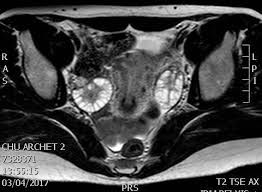

Tu sais on est beaucoup a souffrir du SOPK

( kystes dans les ovaires)

C'est l'une des causes les plus courrantes d'infertilité chez la femme

Le pire c'est que l'on arrive toujours pas a determiner la causalité de cette pathologie..

on dirait des pti oeufs durs dans les ovaires

Je ne sais pas à quoi ressemble les miens, je vais faire une echographie bientot